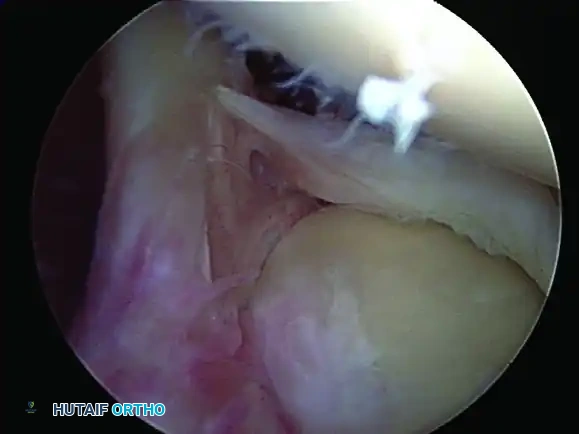

Type III SLAP Lesion

• Pathology: A vertical tear within the substance of the labrum that produces a displaced "bucket-handle" fragment. The biceps anchor and the peripheral labral attachment remain securely fixed to the bone.

Image

• Treatment: The bucket-handle fragment acts as a mechanical irritant within the joint. Provided the biceps anchor is probed and confirmed to be absolutely stable, the treatment of choice is arthroscopic excision (resection) of the torn meniscoid fragment.